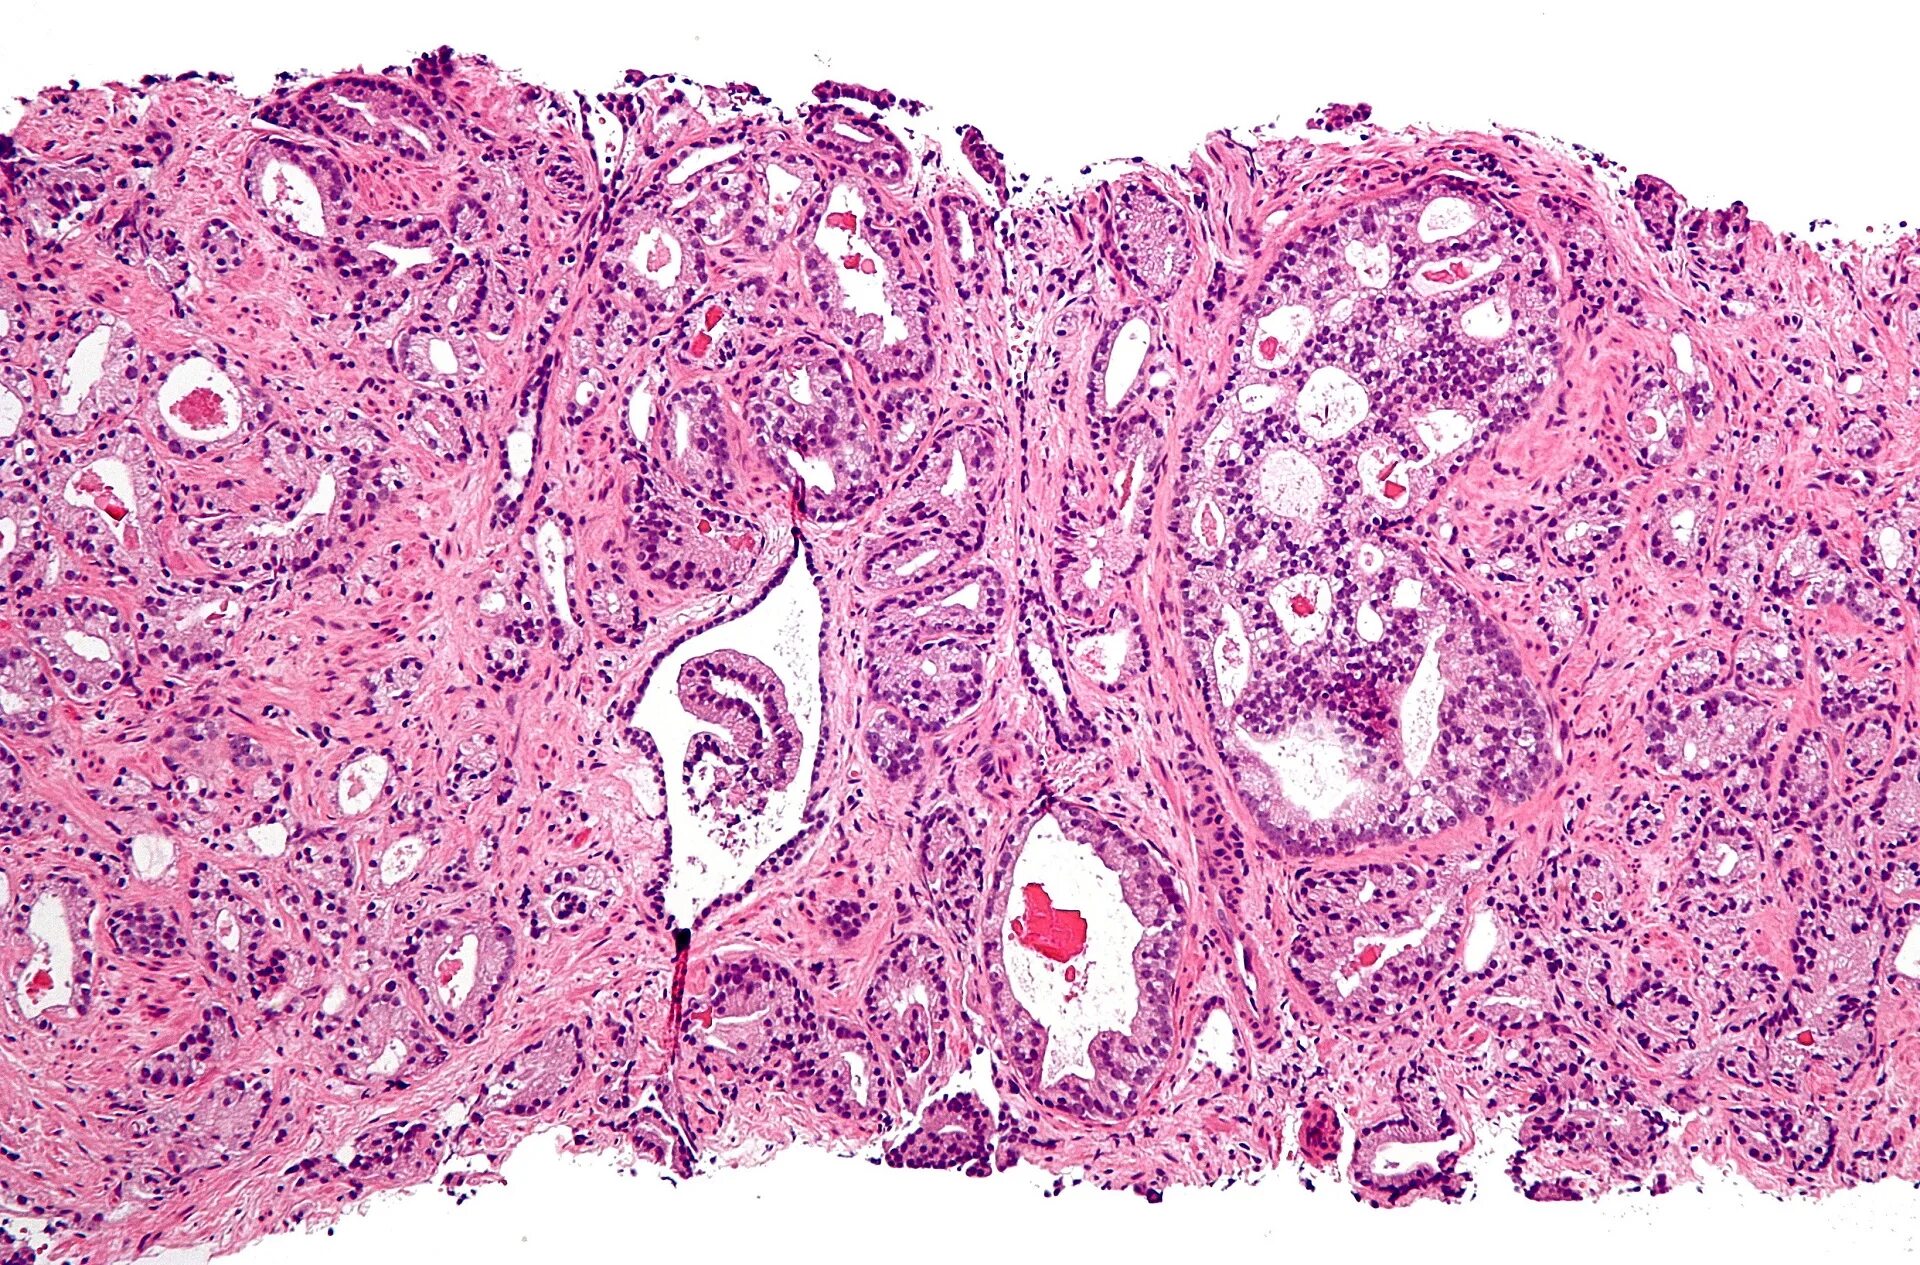

Гистология аденокарциномы